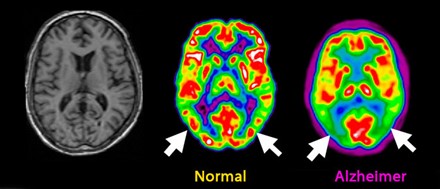

Descrita por primera vez por Emil Kraepelin, fue Alois Alzheimer quien la catalogó con una descripción detallada de los hallazgos neuropatológicos y de las lesiones de los tejidos cerebrales, evidenciando las alteraciones en las fibrillas del citoesqueleto de la neurona en una paciente, Auguste Deter, que estudió hasta la muerte de ésta, analizando su cerebro posteriormente.

Desde 1906 hasta ahora se ha progresado mucho en la descripción de las estructuras que aparecen en los depósitos de amiloide y tau, los genes PSEN1 y PSEN2, el gen de la APOE4, y otras varias hipótesis no confirmadas.